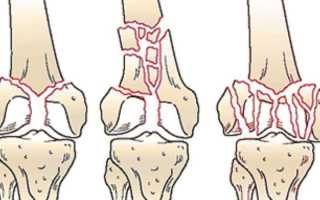

Эпифизарный перелом, в свою очередь, характеризуется тем, что линия перелома проходит полностью или частично через внутрисуставную капсулу. В результате этого патологического процесса могут пострадать все элементы сустава, отвечающие за его подвижность, включая связки, хрящи и кости.

При таких повреждениях часто наблюдается развитие гемартроза – скопление крови внутри сустава из поврежденных сосудов, что происходит вследствие перелома. После того как кровь попадает в капсулу, начинается воспалительный процесс.

Кроме общей классификации переломов, можно выделить и частную, специфичную для внутрисуставных повреждений:

- Если структура сустава осталась неизменной и не нарушенной, такой перелом считается стабильным.

- Если наблюдаются повреждения суставной капсулы, разрывы связок и образование обломков, то это нестабильный перелом.